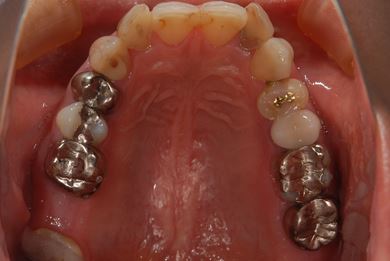

| 治療方針 | 上前歯部分、セラミック治療にて審美的回復を行う。 | ||||||||||||||||||||||||||||||||

| 治療内容 | オールセラミッククラウン3本(オールセラミック用土台3本)、メタルボンドセラミッククラウン1本 | ||||||||||||||||||||||||||||||||